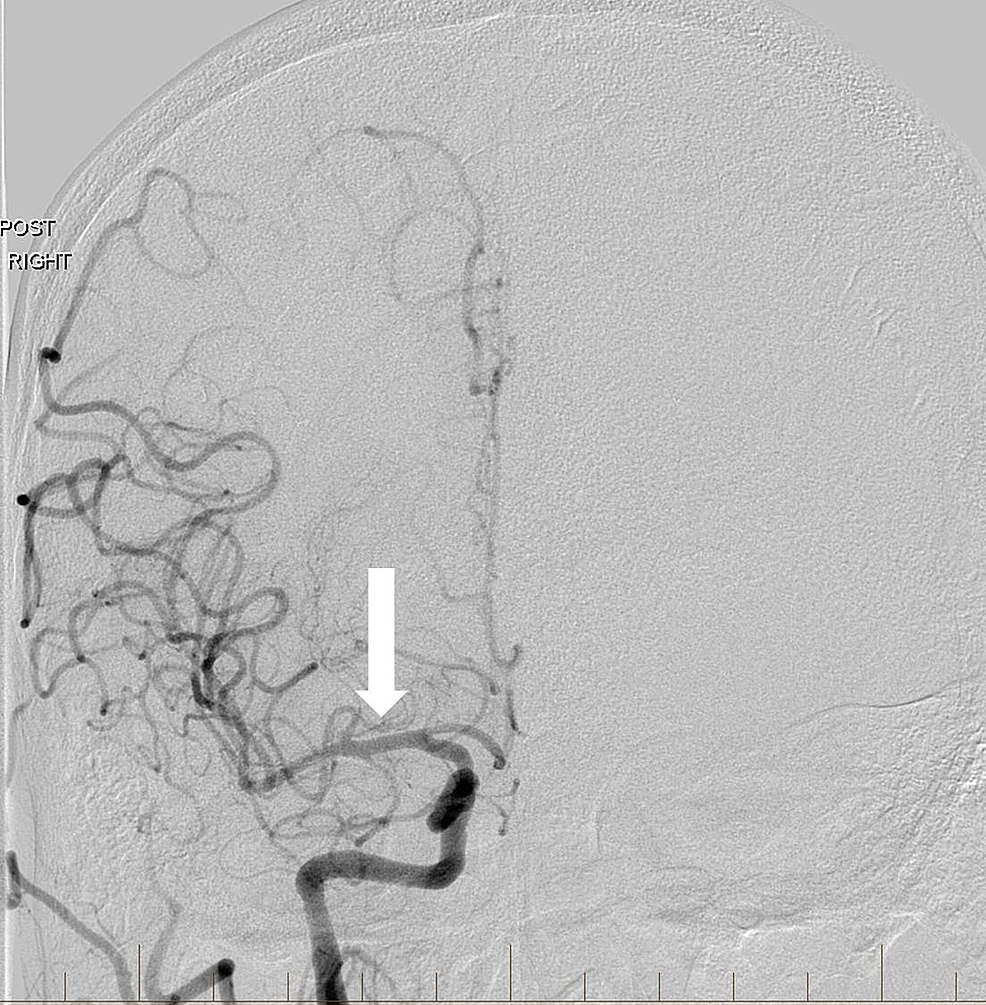

Angioplasty was performed at the level of the severe proximal ICA occlusion using a 4 mm x 20 mm noncompliant balloon. Subsequent angiography demonstrated the progression of contrast into the distal cervical and intracranial segments of the ICA with a persistent severe and irregular stenosis. A decision was then made to stent using distal embolic protection. A 4-mm diameter distal protection device was advanced and deployed in standard fashion within the distal cervical ICA at the level of C1-C2. An eptifibatide infusion was started, and an 8 mm to 6 mm tapered self-expanding carotid stent measuring 40 mm in length was positioned across the lesion and deployed in the standard fashion without angiographic complications. Post-stenting angiography revealed a 90% improvement in the caliber of the occluded vessel without delay in transit time throughout all cervical and intracranial right ICA segments (Figure 2).

The right MCA was then patent with excellent flow to the anterior circulation (Figure 3).